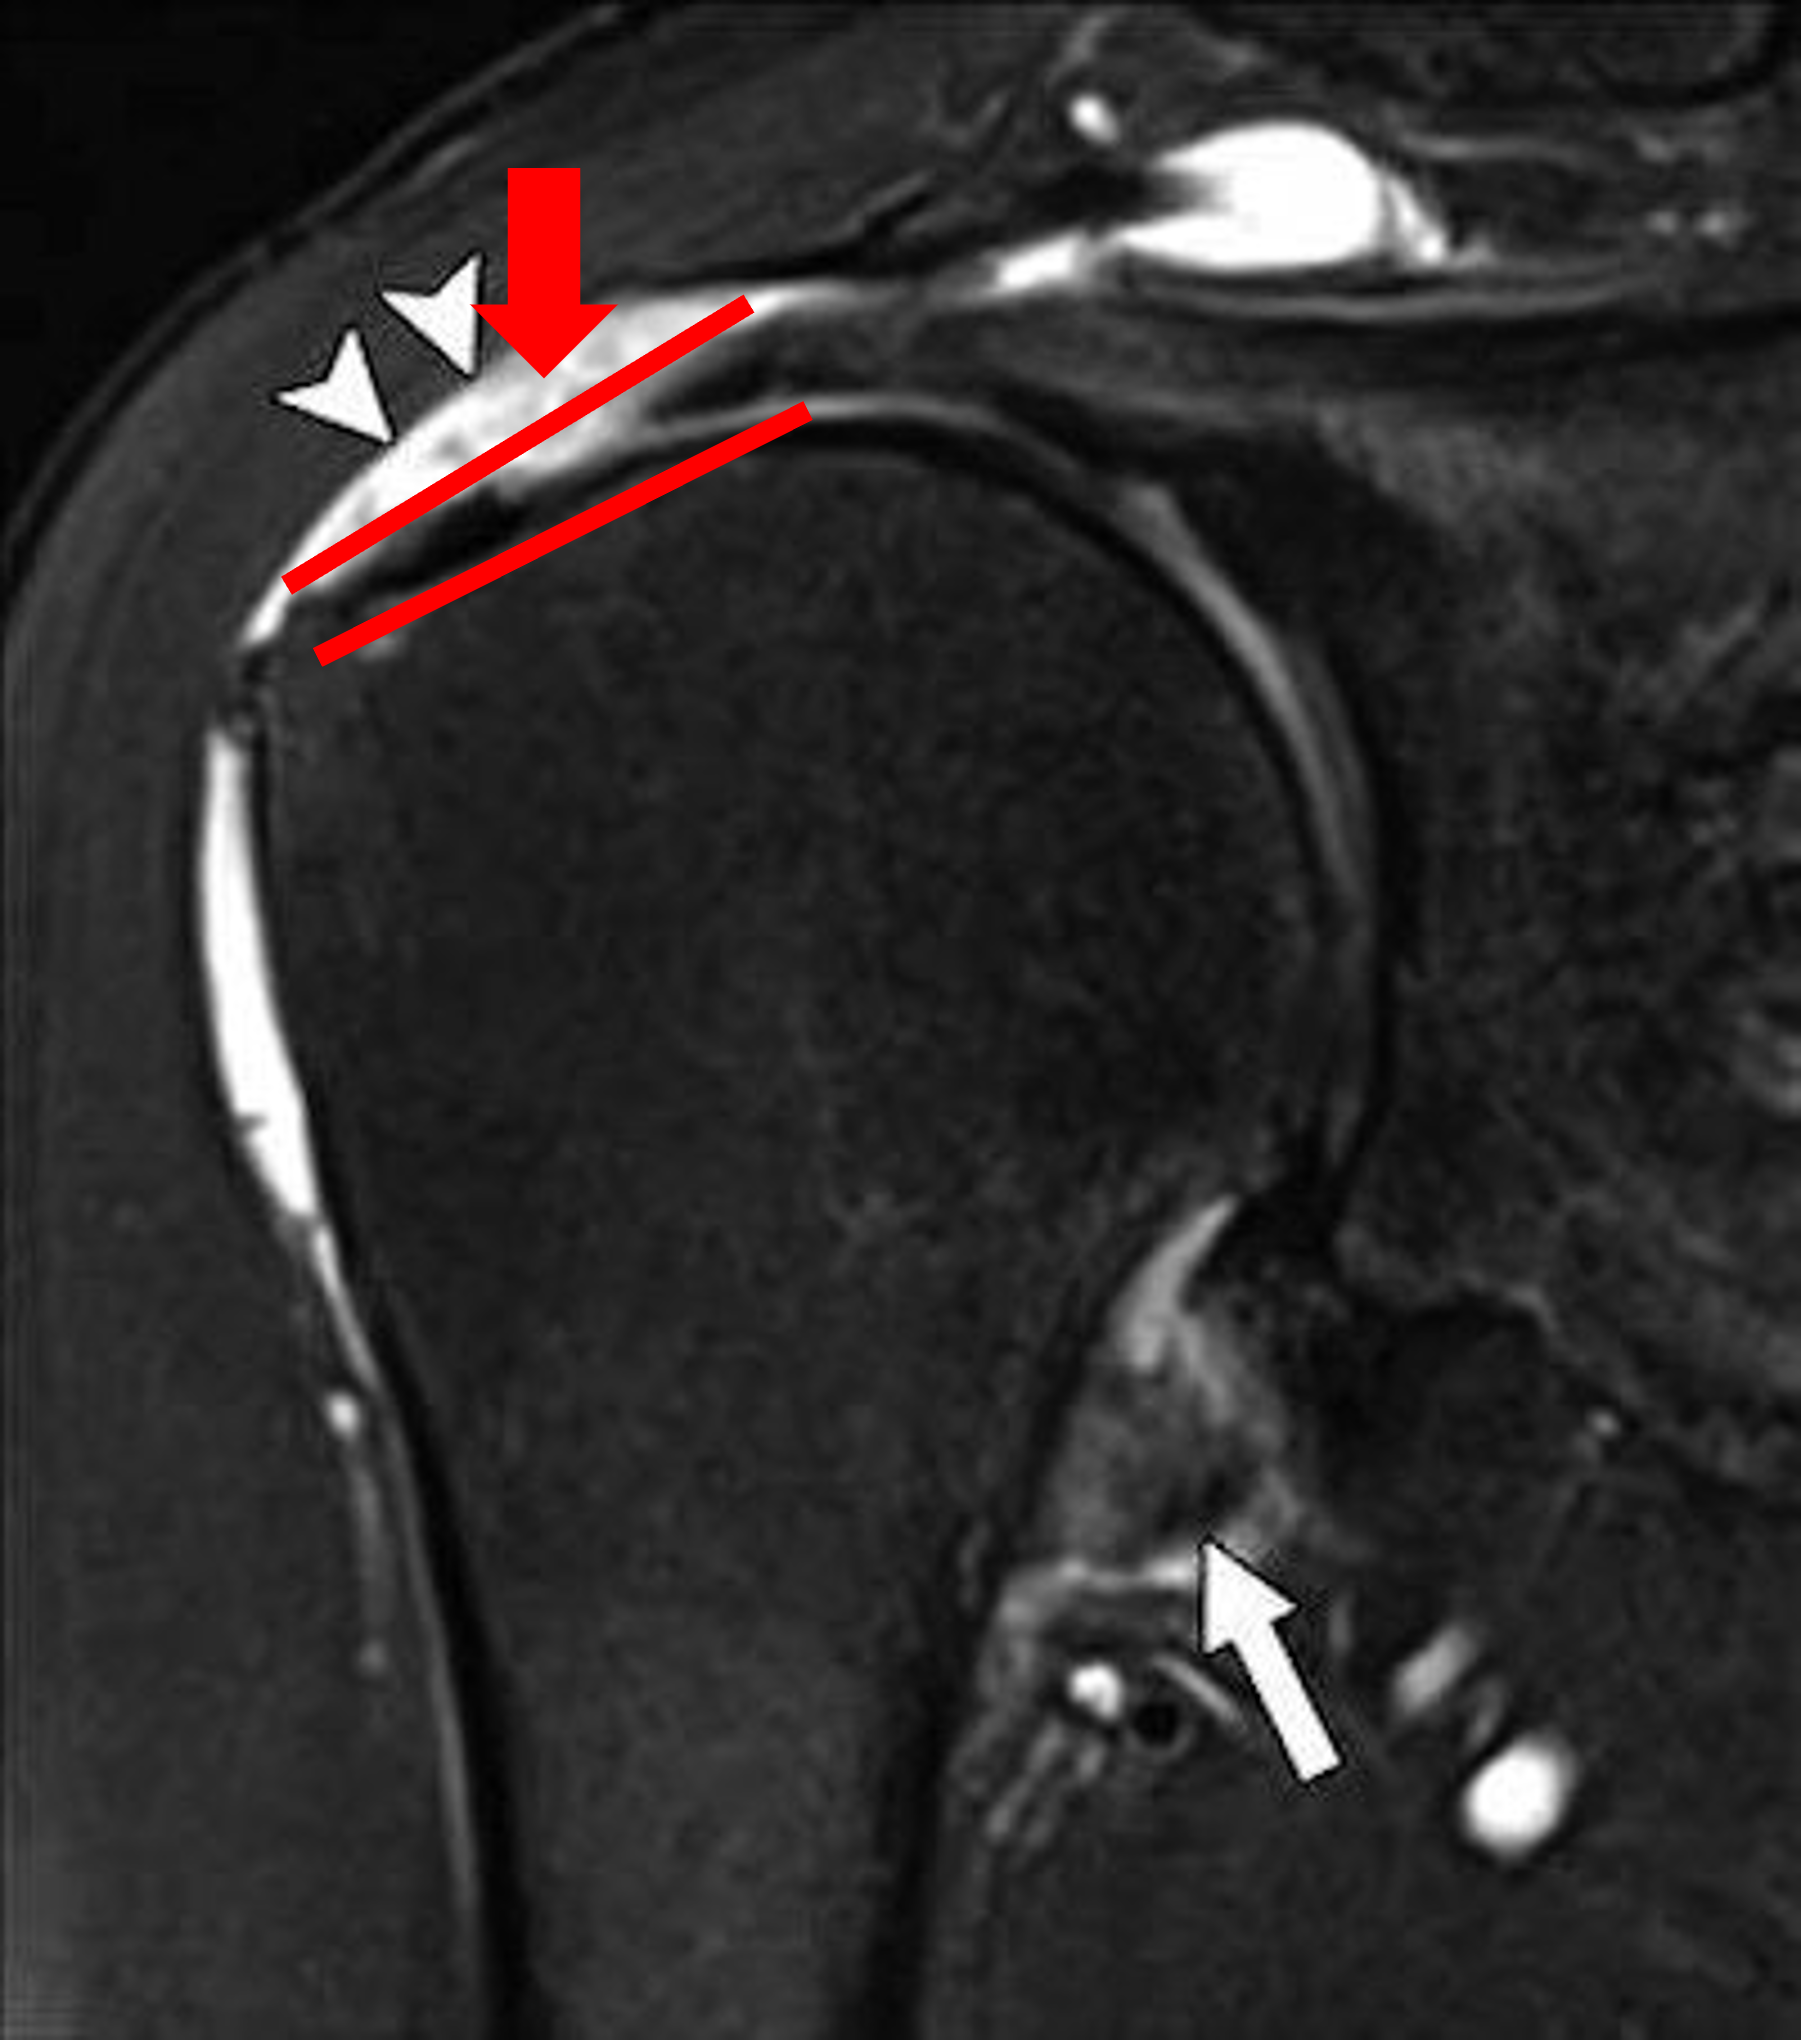

3. MRI :

사실상 회전근개파열을 진단하는데 가장 중요한 진단 방법입니다. MRI는 우리 몸에 있는 물 분자들을 자기장을 이용하여 회전을 주어 그 신호를 이미지로 형상화 하는 기계입니다. X-ray는 X선을 쏴서 발생하는 그림자를 통해 이미지를 만들기에 뼈가 아닌 연부조직들, 즉 근육이나 인대, 관절낭 등은 이미지화 시킬 수가 없다는 점이 한계이지만, MRI는 이러한 연부조직 들 모두 수분을 가지고 있기에 이미지화 할 수 있는 장점이 있습니다.

회전근개파열이 의심되는 환자에서 MRI를 찍는 이유는 진단 자체에만 있는 것이 아닙니다. 진단만을 위한 경우에는 숙련된 초음파 술자의 경우 초음파만으로도 파열을 진단할 수 있기 때문인데요, 그렇다면 MRI는 왜 촬영하는 것일까요?

제가 정형외과 관련된 글을 쓰면서 여러번 반복하여 말씀드린 내용이 있습니다. 진단적 검사는 결국, 치료의 방침, 즉 플랜을 결정하기 위해 시행하는 것입니다. MRI를 찍었을 때와, 찍지 않았을 때, 그 치료방법이나 추후 플랜이 바뀌지 않는다면 굳이 MRI를 비싼 비용을 들여 촬영할 이유가 없을 것입니다. 하지만 MRI결과에 따라 그 플랜이 바뀌게 된다면, 검사를 꼭 해봐야겠죠?

MRI는 회전근개의 손상 부위를 정확하게 이미지화함과 동시에, 파열의 크기, 깊이, 그리고 주변 다른 조직의 손상을 동시에 관찰하게 해줍니다. 이는 결국 파열된 회전근개를 주사치료 정도만 해도 될 것인지, 아니면 파열이 커서 수술적 처치로 봉합을 해야할 것인지를 결정해주는 중요한 자료가 됩니다.